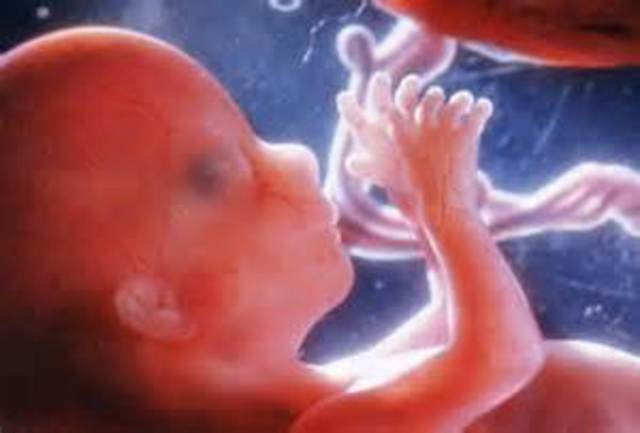

• 26 weeks pregnant

26 weeks pregnant

The network of nerves in your baby's ears is better developed and more sensitive than before. He may now be able to hear both your voice and your partner's as you chat with each other. He's inhaling and exhaling small amounts of amniotic fluid, which is essential for the development of his lungs. These so-called breathing movements are also good practice for when he's born and takes that first gulp of air. And he's continuing to put on baby fat.